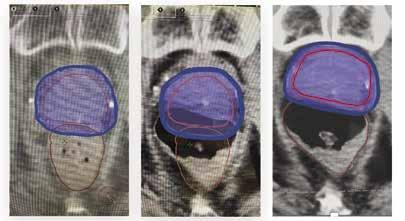

Cancer often develops deep within the body, sometimes near critical organs. From day to day, normal changes such as gas, bloating, or bladder fullness can cause tumors and surrounding healthy organs to shift positions slightly. While traditional radiation machines may detect these changes, they cannot fully adjust their predetermined target zones in real time to account for these position or shape alterations. This can result in a cancer target “miss” or unnecessary radiation given to healthy tissues, thereby increasing side effects.

The Gemini 360 changes that. This advanced system allows the radiation target area to be adapted immediately before treatment delivery should adjustments be required, guaranteeing a precise cancer strike while excluding the surrounding, noncancerous tissues. For patients, this means better cancer outcomes with fewer side effects. The illustration below shows the retargeting benefits of the Akesis 360 for prostate cancer despite an unexpected rectum gas bubble appearing on day two, altering treatment area positioning.

Another major benefit of improved accuracy is time savings. Radiation treatment plans that historically required daily patient visits for multiple weeks can now, in some instances, be completed in as few as five days. This can significantly improve quality of life,

reduce disruption, and allow patients to spend more time at home with their families and support systems.

One recent case using this adaptive technology involved Bill O., a prostate cancer survivor who had to travel to UCLA for his therapy. Bill underwent just five treatments using this advanced approach, reducing his originally suggested treatment protocol by seven weeks without any side effects. His experience highlights the real-world impact of adaptive radiation therapy, which not only improves treatment precision but also shortens treatment timelines for many patients.